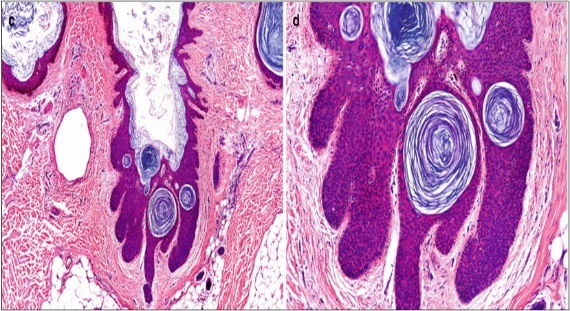

A cogent tissue specimen demonstrates typical features of comedones as follicular ostia distended and impacted with keratin. Significant histological manifestations are the occurrence of enlarged, grouped, distended follicular ostia demonstrating an absence of hair shafts along with impaction of laminated keratin. Base of the follicular invaginations may or may not delineate singular, rudimentary glandular structures. Miniature cysts, cystic invaginations and occasional enlarged cysts can be encountered. Cystic articulations are diverse and preponderantly layered by keratinizing, stratified squamous epithelium. Hyperkeratosis or epidermolytic hyperkeratosis and acanthosis of superimposed epidermis can concur although the lesion is devoid of parakeratosis or dyskeratosis5, 6.

Nevus comedonicus demonstrates immune reactivity to cytokeratin, simulating the expression of normal cutaneous surfaces. Generally encountered within the granular epidermal layer, immune reactivity for filaggrin is demonstrable within the entire epidermal thickness of closed comedones, a molecular which can be implicated in the genesis of nevus comedonicus6, 7. Electron microscopy demonstrates an enhanced quantification of Langerhans cells, numerous kerato-hyaline granules along with an abundance of tonofilaments within upper portion of stratum spinosum. Incompletely differentiated arrector pili muscles are impacted with intracellular glycogen particles6, 7. Figure 1, Figure 2, Figure 3, Figure 4, Figure 5, Figure 6, Figure 7, Figure 8, Figure 9, Figure 10.

Figure 5.Nevus comedonicus clinically demonstrating darkly-stained, grouped, distended, follicular ostia, plugged with keratin, demonstrating a honey-comb pattern14.

Figure 6.Nevus comedonicus delineating dilated, plugged, follicular ostia, keratinous substance and a layering with a hyperkeratotic, stratified squamous epithelium[15.

Figure 7.Nevus comedonicus with an aggregation of dilated, plugged follicular ostia, keratinous flakes and an intensely hyperkeratotic stratified squamous epithelial layer16.

Figure 8.Nevus comedonicus exhibiting aggregates of distended follicular ostia, keratin plugging and a lining of hyperkeratotic stratified squamous epithelium16.